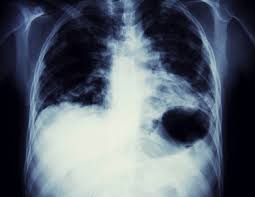

A series of mutations in the dna of the cell creates cancer. Breathing high levels of asbestos can lead to mesothelioma or lung cancer. Lung cancer originates in the lungs, but it can spread. Abnormal cells grow and can form tumors. Diseases that attack these organs can cause serious health problems, so the sooner you know about them,. A diagnosis of lung cancer naturally causes some overwhelming emotions, but you don't have to let those emotions get the best of you. It was once used widely. Here we look at some of the key symptoms of this disease to watch out for.

Abnormal cells grow and can form tumors. Asbestosis is a chronic lung disease caused by the inhalation of asbestos fibers. Adenocarcinoma cancers being usually in one of the following organs: Breathing high levels of asbestos can lead to mesothelioma or lung cancer. Lung cancer has two broad types: Asbestosis is a chronic lung disease caused by scarring of lung tissue, which stems from prolonged exposure to asbestos. A diagnosis of lung cancer naturally causes some overwhelming emotions, but you don't have to let those emotions get the best of you. When it comes to monitoring your health, your heart and lungs are right at the top of the list of important organs you should focus on.

Here we look at some of the key symptoms of this disease to watch out for. When it comes to monitoring your health, your heart and lungs are right at the top of the list of important organs you should focus on. Most cases of lung cancer are associated with. Asbestosis is a chronic lung disease caused by scarring of lung tissue, which stems from prolonged exposure to asbestos. Asbestos is the name of a group of minerals with thin fibers. Lung cancer originates in the lungs, but it can spread. Breathing high levels of asbestos can lead to mesothelioma or lung cancer. Lung cancer is a serious illness which none of us wish to face. The general term "lung cancer" actually covers a few very different versions of the disease. Asbestosis is a chronic lung disease caused by the inhalation of asbestos fibers. It was once used widely. A diagnosis of lung cancer naturally causes some overwhelming emotions, but you don't have to let those emotions get the best of you. Lung cancer is a leading type of cancer — and a leading killer — in the united states every year.